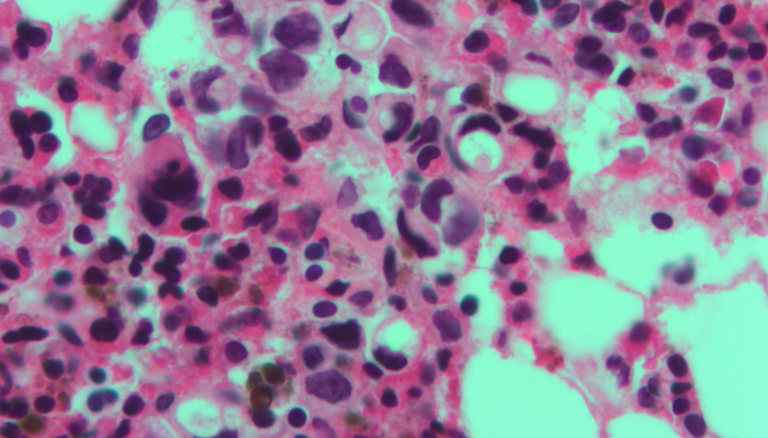

Pictured: Micrograph of signet ring cells (arising from breast). H&E stain. Nephron/Creative Commons.